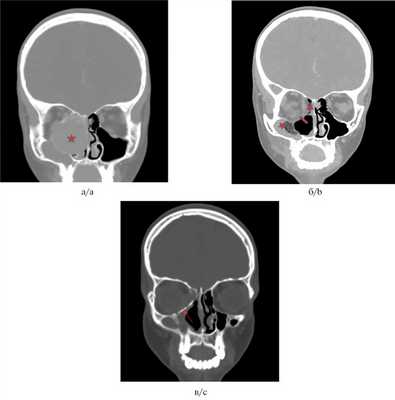

Для ЮПОФ характерен симптом «матового стекла», для ЮТОФ — хаотичное включение кальцинатов (рис. 1, а, 2, а) [9].

![]()

Рис. 1. Клинический случай 1. КТ, коронарная проекция.

а — ЮТОФ решетчатого лабиринта с распространением в орбиту, на основание черепа, в полость носа и верхнечелюстную пазуху. Звездочкой обозначено образование; б — состояние после удаления ЮОФ. Стрелкой показан дефект нижнемедиальной стенки орбиты, звездочками показаны послеоперационные изменения в решетчатой и верхнечелюстной пазухах; в — КТ через 5 мес после удаления ЮОФ с реконструкцией нижнемедиальной стенки орбиты. Стрелка указывает на пластину. Нет данных за рецидив.![]()

Клинический случай № 1

Пациент, 12 лет, поступил в НМИЦ ДГОИ с жалобами на выстояние глазного яблока справа, затруднение носового дыхания. Месяц назад был прооперирован в другом ЛПУ — было произведено трансназальное эндоскопическое субтотальное удаление образования. По результатам КТ при поступлении: данные свидетельствуют о продолженном росте опухоли.

Пациенту было выполнено радикальное удаление ЮТОФ трансназальным эндоскопическим методом. По результатам КТ после операции: данных за резидуальную опухоль нет, однако после операции у пациента возникла диплопия. Для коррекции диплопии проводилась реконструкция нижнемедиальной стенки орбиты титановой пластиной с положительным эффектом. На рис. 1 представлены КТ-снимки пациента до и после хирургического лечения.